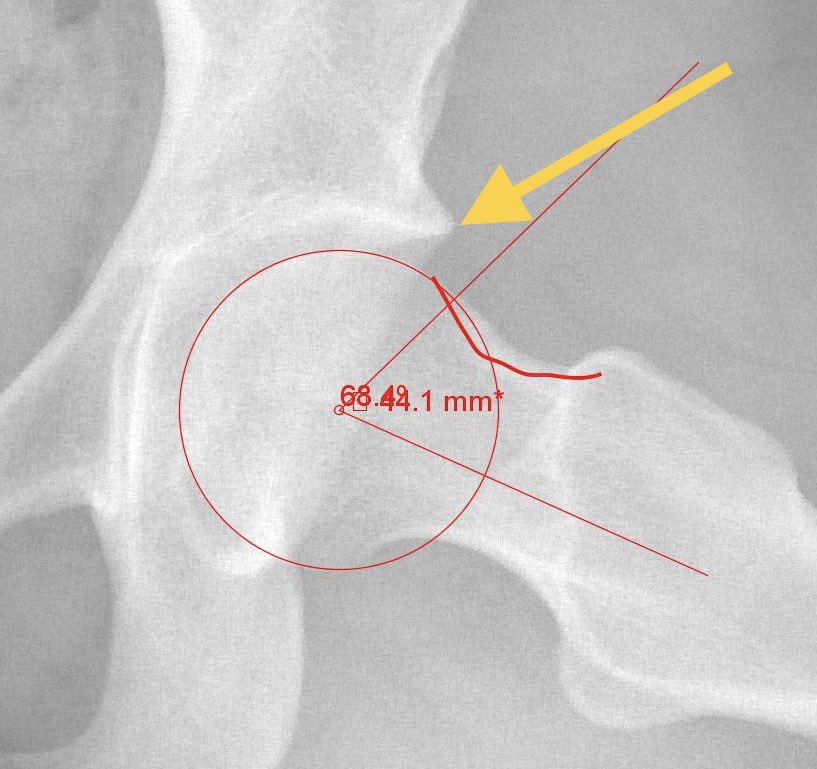

Here’s a pic that shows both. Top arrow is pincer, bottom arrow is cam.

The surgeon needs to carefully evaluate the bony structure (same patient’s X-Rays, which shows an increased alpha angle (cam #HipFAI) and extra bone off the acetabulum (pincer-yellow arrow)